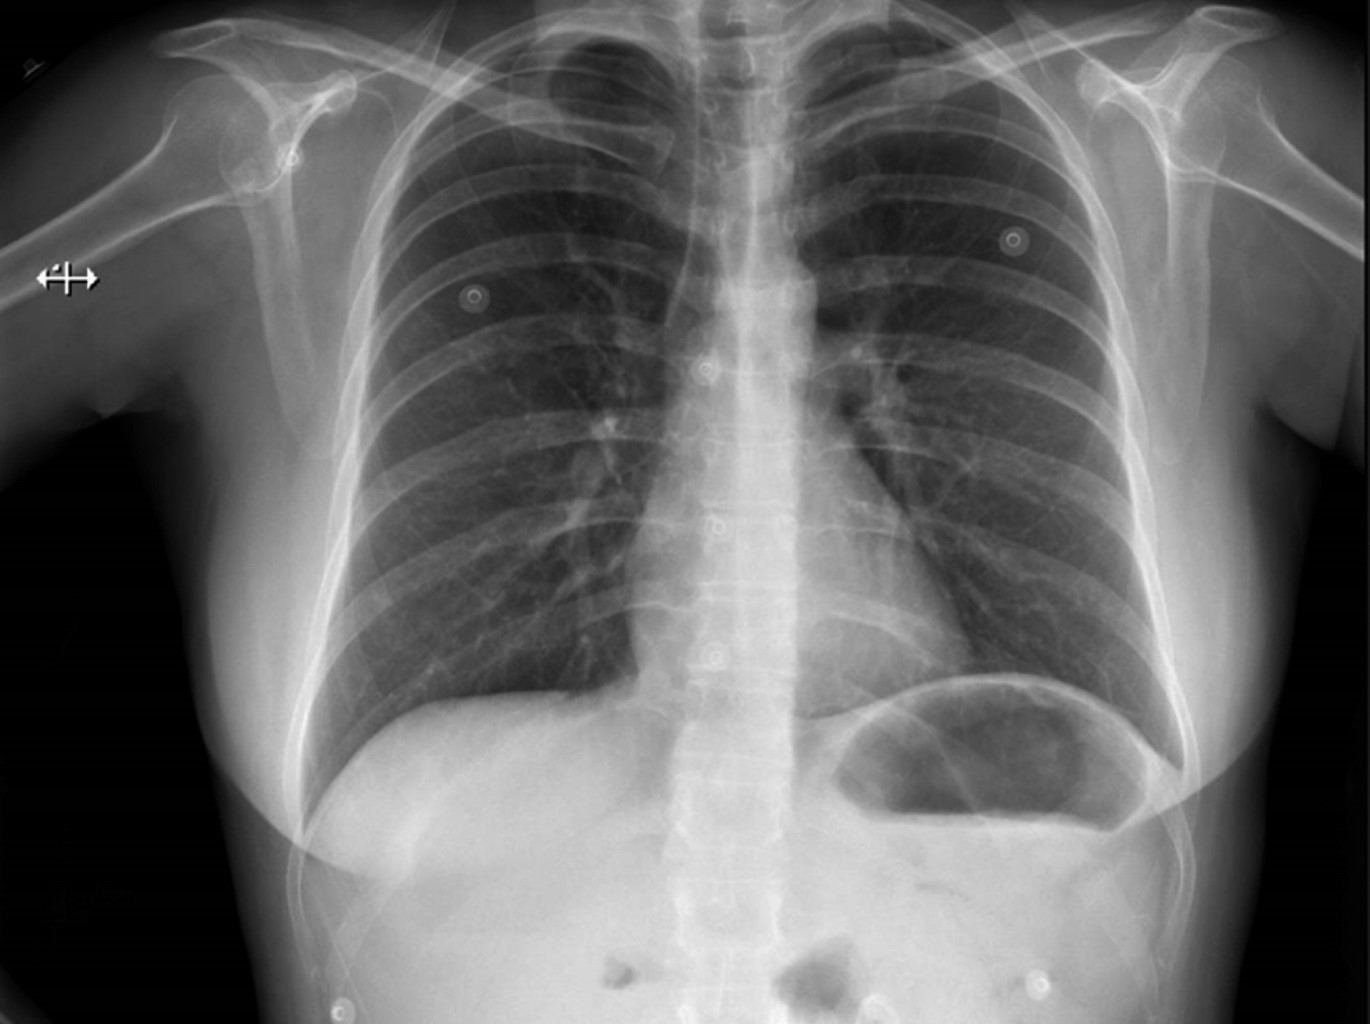

Una mujer de 47 años de edad sin antecedentes médicos se sometió a cirugía endourológica programada. Al ingreso a quirófano, se encontraba en buen estado general, con signos vitales y exploración física normales. Se aplicó anestesia general balanceada, realizando inducción con fentanilo, propofol, rocuronio y durante laringoscopia sin evidencia de anomalías. Orotubación se realizó sin complicaciones al primer intento con hoja número 3 y tubo número 7, cursa hemodinámicamente estable, sin necesidad de apoyo vasopresor con solución Hartmann intravenosa a 20 mL/h sin necesidad de mayor reanimación hídrica, ventilación de protección tidal, mantenimiento con sevorane y fentanilo en infusión calculado a 2 μg/kg/h, ventilación pulmonar simétrica y valores adecuados en capnografía postintubación. Durante el procedimiento quirúrgico sin aumento de presiones o desacoplamiento a ventilación mecánica. La paciente presentó agitación espontánea al recobrar conciencia realizando esfuerzos inspiratorios importantes con laringoespasmo breve de cuarenta segundos. La extubación presentó disminución de agitación y sin deterioro del patrón respiratorio; durante la hora de vigilancia postoperatoria, sin deterioro cardiorrespiratorio. Sin embargo, dos horas posteriores a extubación, la paciente mostró signos de dificultad respiratoria: taquipnea, uso de musculatura accesoria, desaturación al 70% al aire ambiente, estertores crepitantes bilaterales; radiografía de tórax portátil reveló evidencia de edema agudo pulmonar (Figura 1). La administración de oxígeno suplementario logró aumentar saturación hasta 92%. Ante sospecha de edema pulmonar de presión negativa, se realizaron ecocardiograma transtorácico y angiotomografía de tórax, sin evidencia de falla cardiaca ni tromboembolia pulmonar. Se optó por utilizar puntas nasales de alto flujo, diurético de asa, nebulizaciones con β-agonistas y terapia pulmonar. La paciente evoluciona de manera satisfactoria (Figura 2), dándose de alta al tercer día postoperatorio.

Figura 1